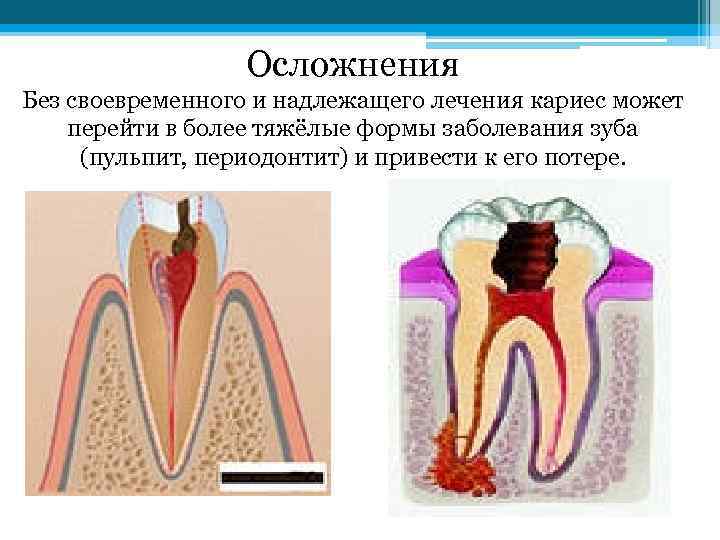

Осложнения Без своевременного и надлежащего лечения кариес может перейти в более тяжёлые формы заболевания зуба (пульпит, периодонтит) и привести к его потере.

Осложнения Без своевременного и надлежащего лечения кариес может перейти в более тяжёлые формы заболевания зуба (пульпит, периодонтит) и привести к его потере.